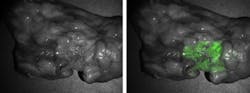

Researchers at the University of Pennsylvania's Perelman School of Medicine (Philadelphia, PA) used real-time fluorescence imaging during surgery to identify lung cancer cells. By using a targeted molecular contrast agent, lung adenocarcinomas fluoresced during pulmonary surgery.

Upon opening the chest cavity, the primary lesion was located using traditional methods of visual inspection and manual palpation. The cancer was imaged and photodocumented with a fluorescence imaging system (Quest Medical Imaging's Artemis fluorescence imaging system) and the FloCam system developed in their laboratory.

Of the remaining 43 tumors, 39 appeared fluorescent after the overlying tissue was opened and the tumor exposed. The fluorescence was uniform across the tumor's surface, and the demarcation between tumor and normal surrounding tissue was clearly visible. On average, the optical imaging was quick, ranging from five to 15 minutes.